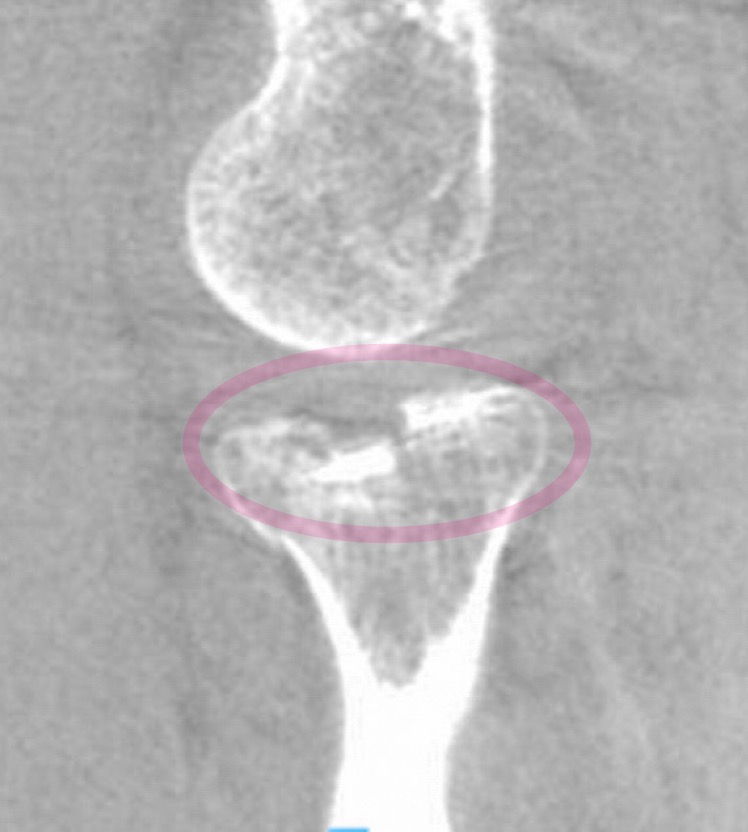

Kävin Mehiläisessä, missä lääkäri passitti röntgeniin. Kuvat kertoivat karua kieltään siitä, miten kauniisti olin onnistunut paskomaan värttinäluuni. Oli se sitten kivi tai ihan vain vääntymä, kuka tietää, mutta värttinäluun pää oli useamman millimetrin painuksissa. Juuri sen verran liikaa, että leikkaukseenhan minut passitettiin.